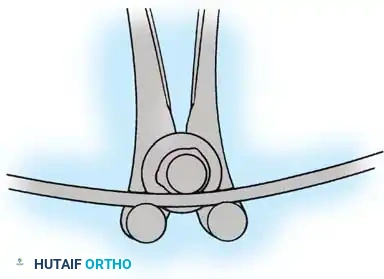

2. Biomechanical Stability: Rigid segmental instrumentation to neutralize micromotion.

Biomechanics of Bone Grafting

Bone graft incorporates most effectively under compressive loads and is biologically disadvantaged in environments of distraction. Therefore, in scoliosis correction, if autogenous bone is limited, it should be preferentially concentrated on the concave side of the curve, which is subjected to compressive forces, rather than the convex side, which experiences tension. Furthermore, the farther the fusion mass is placed from the instantaneous axis of rotation, the more effectively it will neutralize movement across that axis.